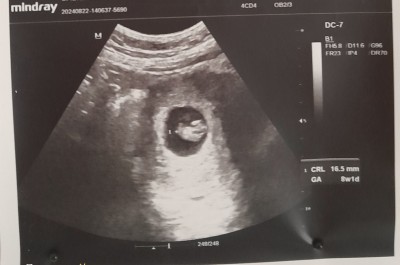

Kızlar bu ultrasyon resmi Yenı degil ama merak ediyorum anlayan varmı bu muayene de ogrencz ınsallah

Gebelik haftası 11